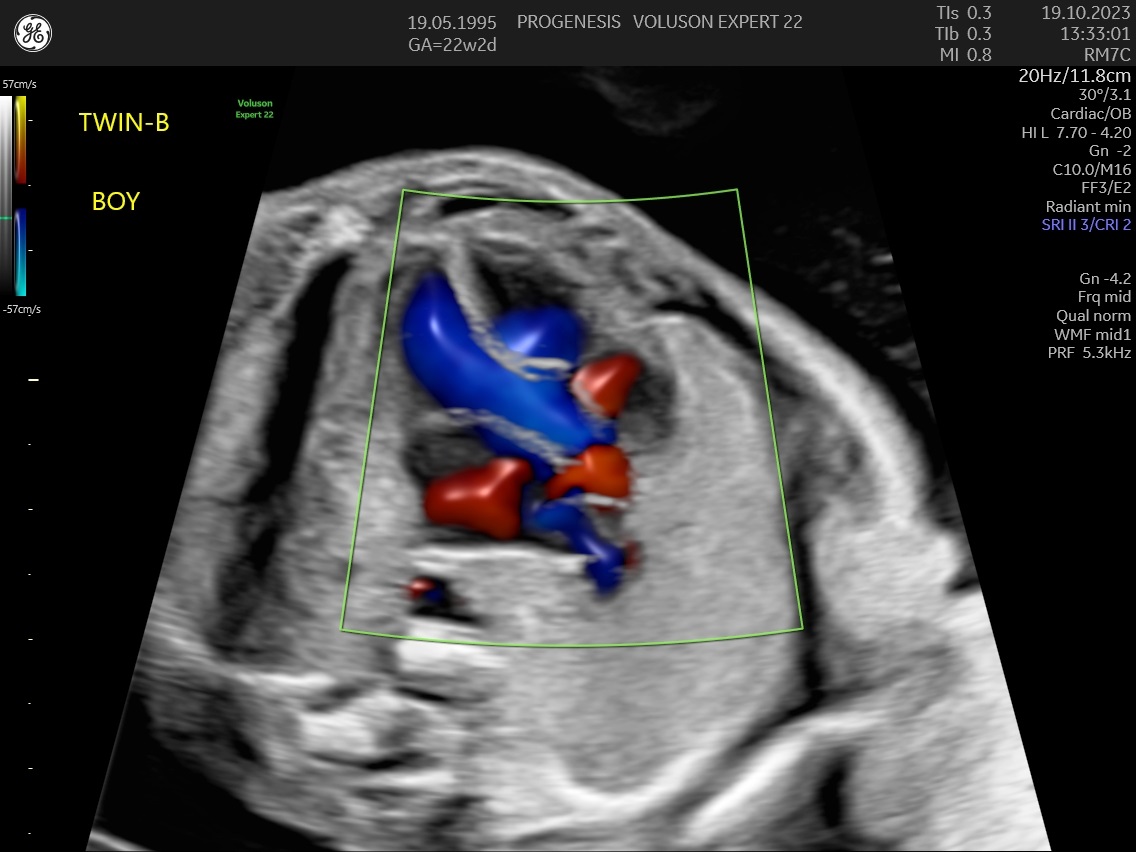

α) Η λεπτομερής αξιολόγηση της εμβρυϊκής ανατομίας, όπου αναγνωρίζονται τυχόν ανατομικές ανωμαλίες.

γ) Ο έλεγχος της ανάπτυξης του εμβρύου, του πλακούντα, του ομφαλίου λώρου και του αμνιακού υγρού.

ε) Ο υπολογισμός της πιθανότητας προεκλαμψίας και ενδομήτριας καθυστέρησης της ανάπτυξης του εμβρύου.

Η μέτρηση των αντιστάσεων στις αρτηρίες της μήτρας, θα εντοπίσει τις μητέρες που έχουν αυξημένη πιθανότητα να εμφανίσουν υπέρταση ή προεκλαμψία στη κύηση ή και πλακουντιακή δυσλειτουργία που θα οδηγήσει σε ελλάτωση της εμβρυϊκής ανάπτυξης (μικρό έμβρυο).